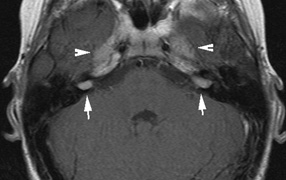

The incidence of optic pathway gliomas in NF1 is difficult to estimate, as the majority are asymptomatic and do not affect vision. In NF1, radiographic evidence of an optic nerve glioma occurs in 15% of patients.64,65 Most tumors are neither suspected historically nor detected by ophthalmic examination.65 Even when optic nerve gliomas become clinically detectable, visual function often remains stable in the absence of any intervention.66,67 Thus routine computed tomography (CT) imaging, even in patients with a known optic nerve glioma, is controversial. The potential risks of repeated radiation exposure in a child with a tumor-suppressor gene defect is a consideration. MRI studies are more revealing than CT but may require sedation or anesthetic and are costly. An MRI is often recommended at the time of diagnosis, but in most cases routine “follow-up” MRIs are unnecessary. Annual ophthalmic clinical examination for relative afferent pupillary defect (RAPD), visual acuity, visual fields, color vision, and funduscopy is usually all that is required, as no therapeutic action is likely to be taken unless there is significant and progressive visual involvement. Optic nerve gliomas may involve the optic chiasm and be associated with endocrine disorders or nystagmus.68–70 Surgical excision of chiasmal gliomas (Fig. 6) carries a high risk of visual loss. Invasion of the hypothalamus or the third ventricle carries a poor prognosis, with greater than 50% 15-year mortality rate.71 One review of radiation treatment for chiasmal gliomas collated data from small case series and found no significant long-term improvement in visual function, progression, or mortality with radiation treatment.71 Other reports suggest that radiation doses over 4500cGy improve symptoms and slow progression of chiasmal gliomas over several years.72 Adequate tumor coverage by radiotherapy results in irradiation of normal brain and nearly all children need hormone replacement.73 Chemotherapy is an alternative.74,75